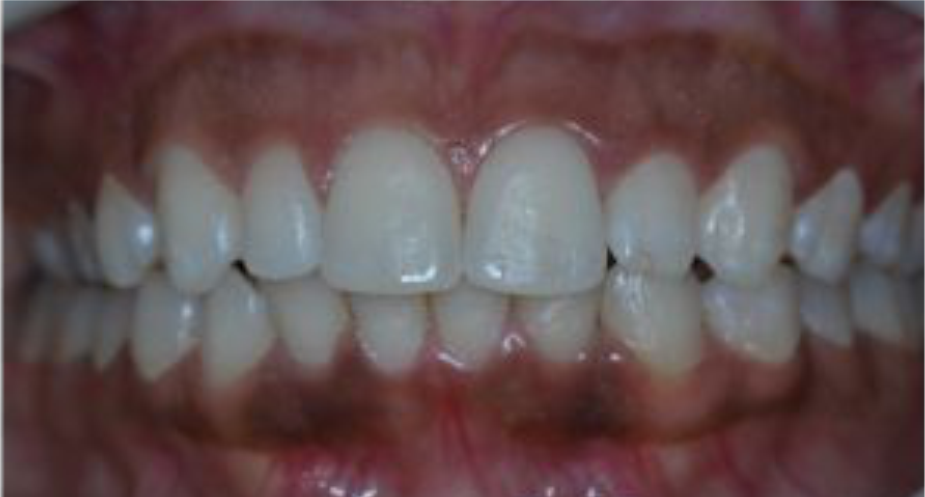

A gengivite é caracterizada pela inflamação do tecido gengival, causada pela proliferação de bactérias. Quando a higiene bucal não é feita da forma adequada ocorre o acúmulo de bactérias que leva a formação de uma placa bacteriana, uma película viscosa e incolor. Em um primeiro momento, esta placa é de fácil remoção, com o passar do tempo ela se calcifica e adere firmemente ao dente (Tártaro). Caso não seja removida, essa placa pode liberar toxinas que afetam a gengiva e desencadeiam o problema.

Inflamação

Gengiva inflamada;

Vermelha escura;

Inchada;

Dolorida;

Sangramento e até supuração ao toque;

Pode haver Mau Hálito;

NÃO há Perda Óssea.